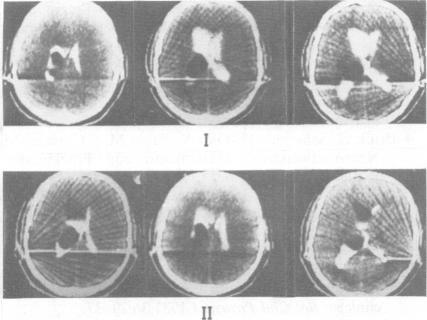

The selective use of praziquantel for the treatment of brain cysticercosis in human beings is described, based upon the results of clinical tests conducted during a 2 year period. Forty patients with clinical diagnosis of cysticercosis, confirmed and documented by CT, were treated. They are divided into four groups, representative of the various forms of the disease. The results assessed by clinical evaluation and sequential CT, give a ten point criterion of the indications for praziquantel.

基于两年期间进行的临床试验结果,描述了吡喹酮在治疗人类脑囊尾蚴病中的选择性应用。对40例经CT确诊并记录的临床诊断为囊尾蚴病的患者进行了治疗。他们被分为四组,代表了该病的各种形式。通过临床评估和连续CT评估的结果给出了吡喹酮适应症的十点标准。